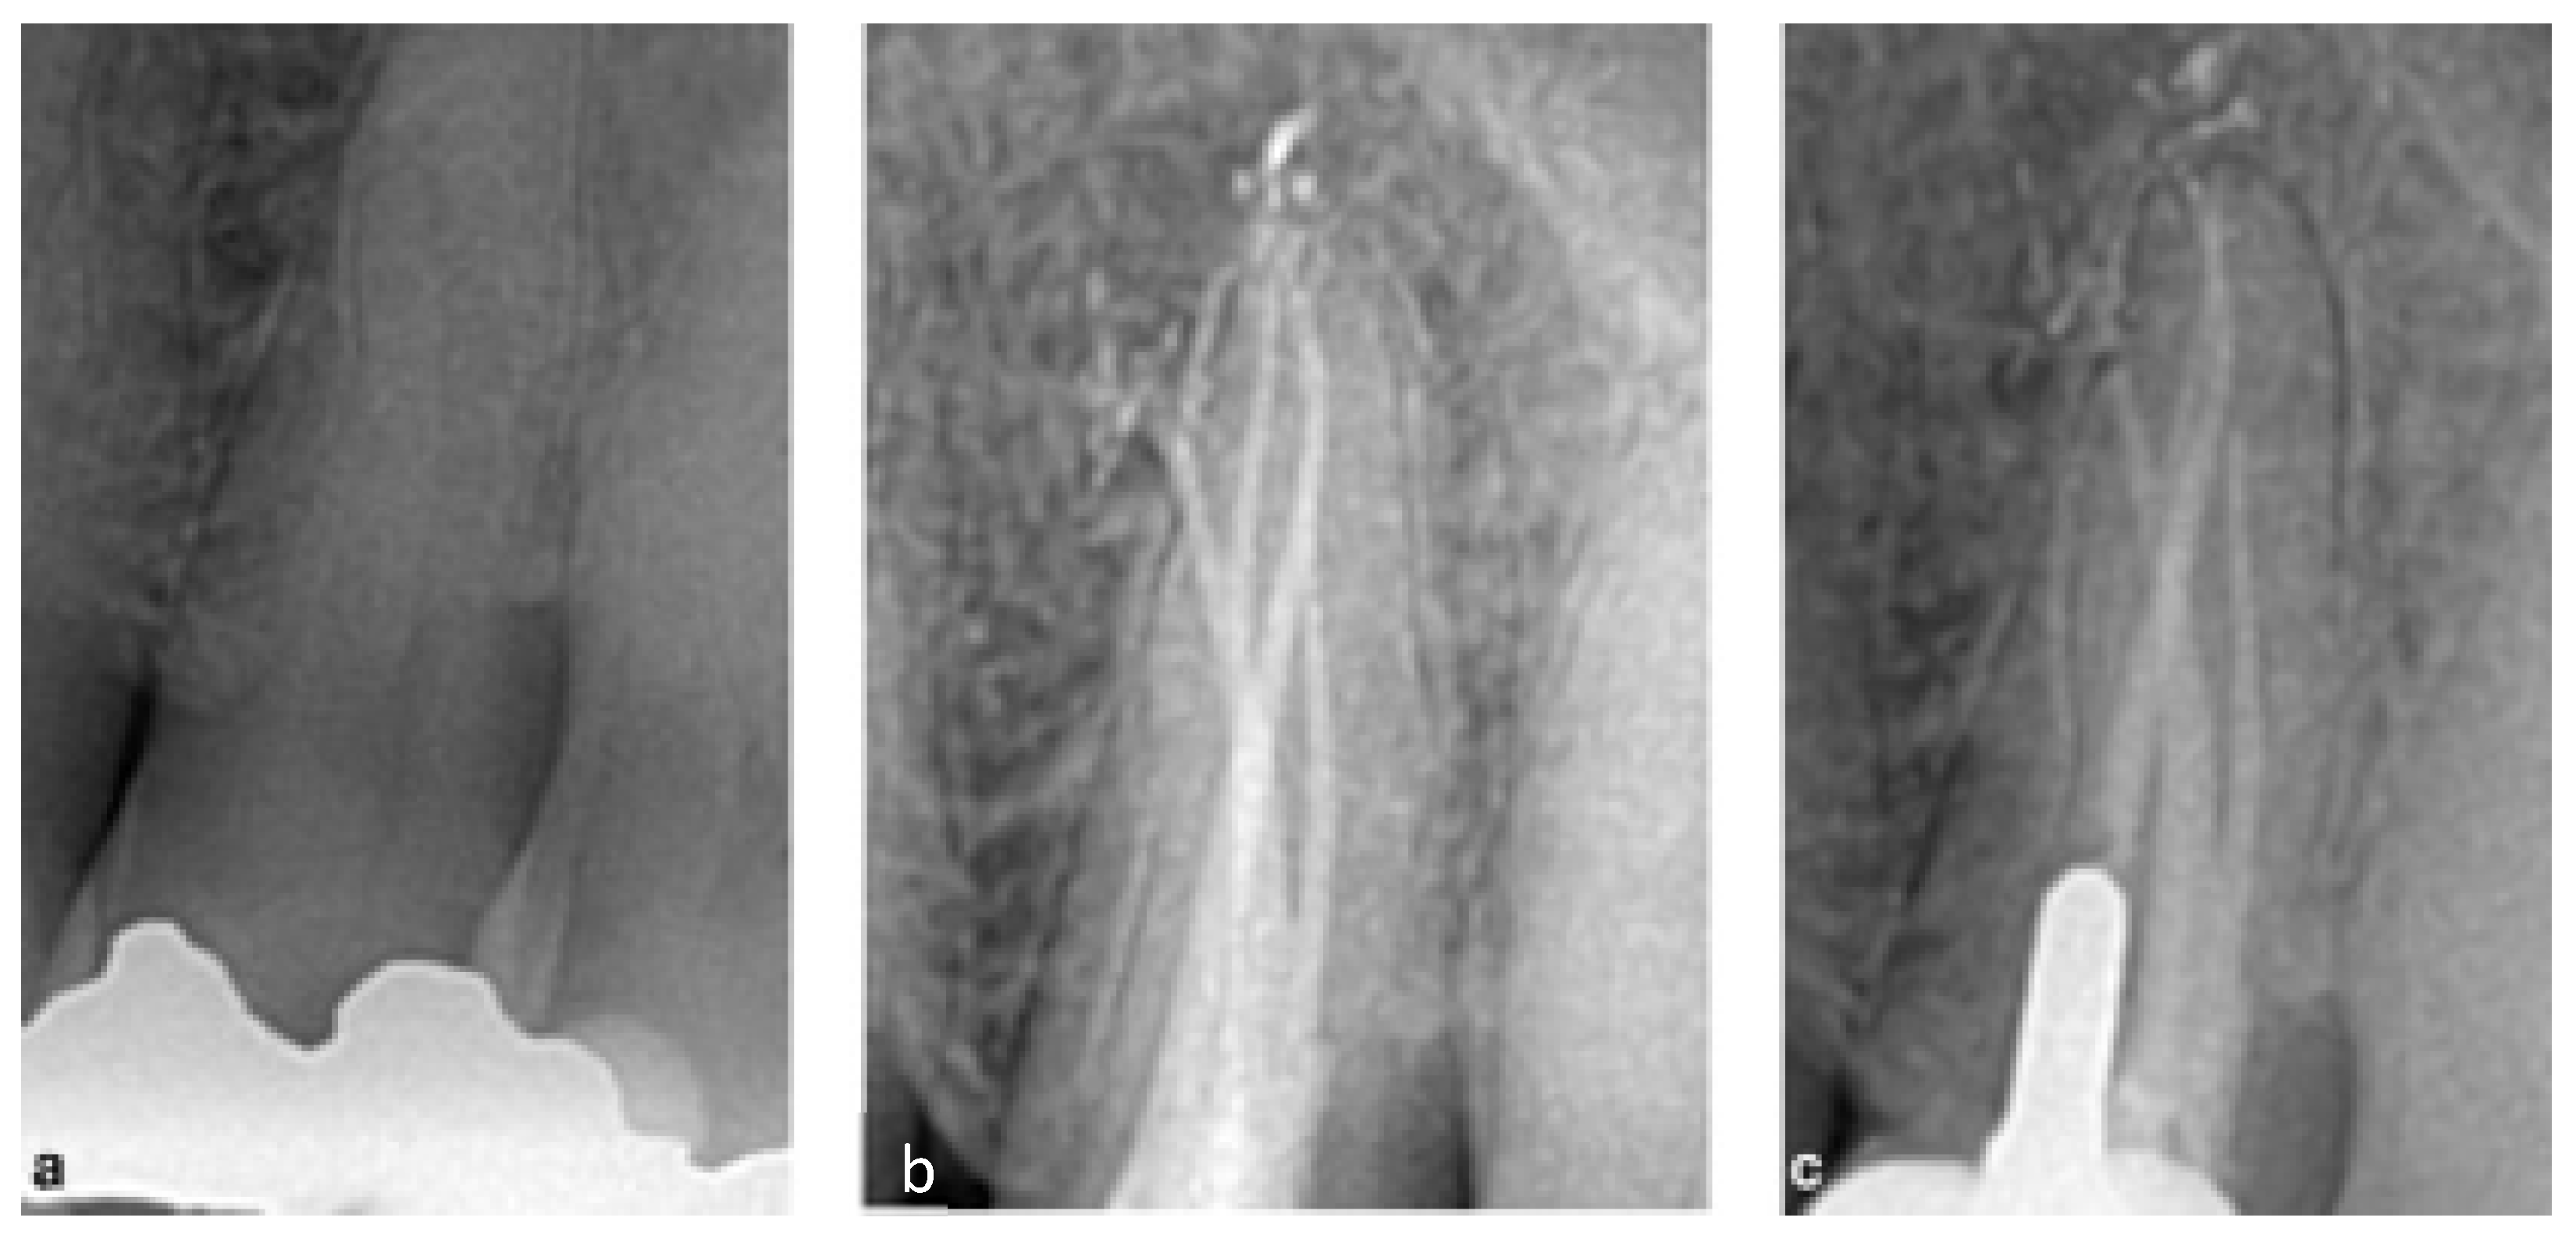

2.3. CASE 3